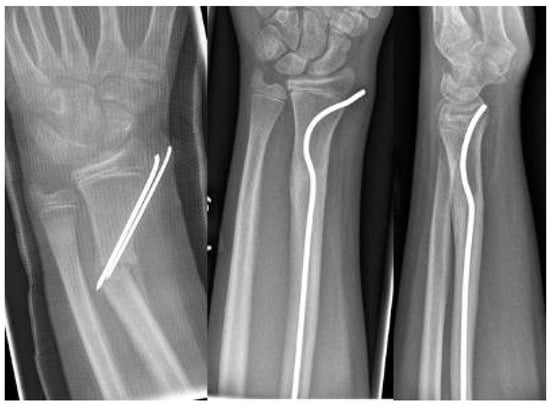

Scheme 2. 2-year-old boy with secondary displacement.

The youngest patient was a two-year old boy, who presented with an unacceptable secondary displacement two weeks after trauma and, thus, this fracture became a rare indication for osteosynthesis in this age group (Scheme 2). The eldest was 17 years of age and did not show epiphyseal plates anymore (Scheme 3). This patient, however, suffered a new trauma 3 weeks later and underwent a redo-procedure in another hospital and, thus, was lost to follow-up. We even treated an open forearm fracture (on the ulnar side) with this technique (Scheme 4), leaving the fracture of the ulna to spontaneous healing and correction. This was because the risk of osteomyelitis due to intramedullary nailing of the open ulnar fracture to achieve a “nice X-ray” was estimated to be much higher than the risk of a remaining misalignment. Even a redo-procedure of a fracture that we had seen for the first time 4 weeks after an unacceptable K-wire osteosynthesis was successful, this time using a modification of the technique with a bend, rather than a kink distal to the fracture. Please note that the pre-bent nail pushed the 4-week-old fracture into a correct position without open reduction (Scheme 4). Last but not least, curiously, we saw one patient who suffered identical fractures in both arms, so we could perform the procedure twice in one operation (Scheme 5).